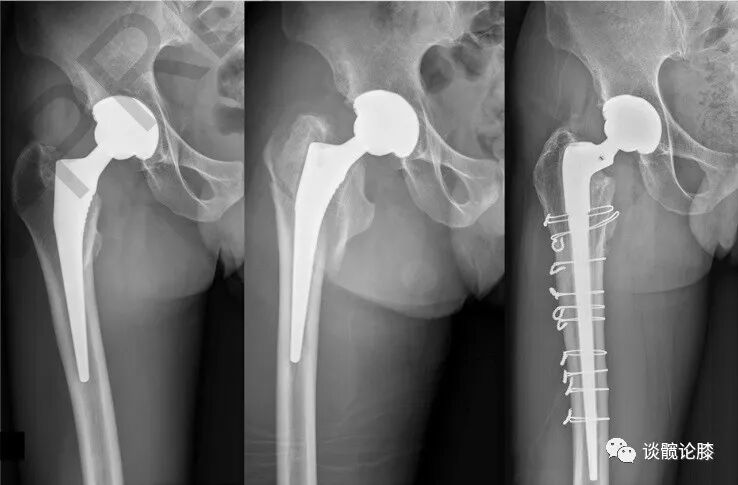

随访期间无陶瓷碎裂,5(5/85,5.9%)髋出现异响(吱吱声),3髋出现假体周围骨溶解(2髋位于股骨柄周围,Gruen分区 1和 7区,图1;1髋位于髋臼周围,DeLee -Charnley分区 2区,图2)。1例因Vancouver B2型股骨假体周围骨折而翻修(图3);1例合并系统性红斑狼疮的患者因假体周围关节感染而接受了清创术。任何原因导致再次手术的存活率为92.4%(95%置信区间为82.4%至100%)。

图3.Vancouver B2型股骨假体周围骨折